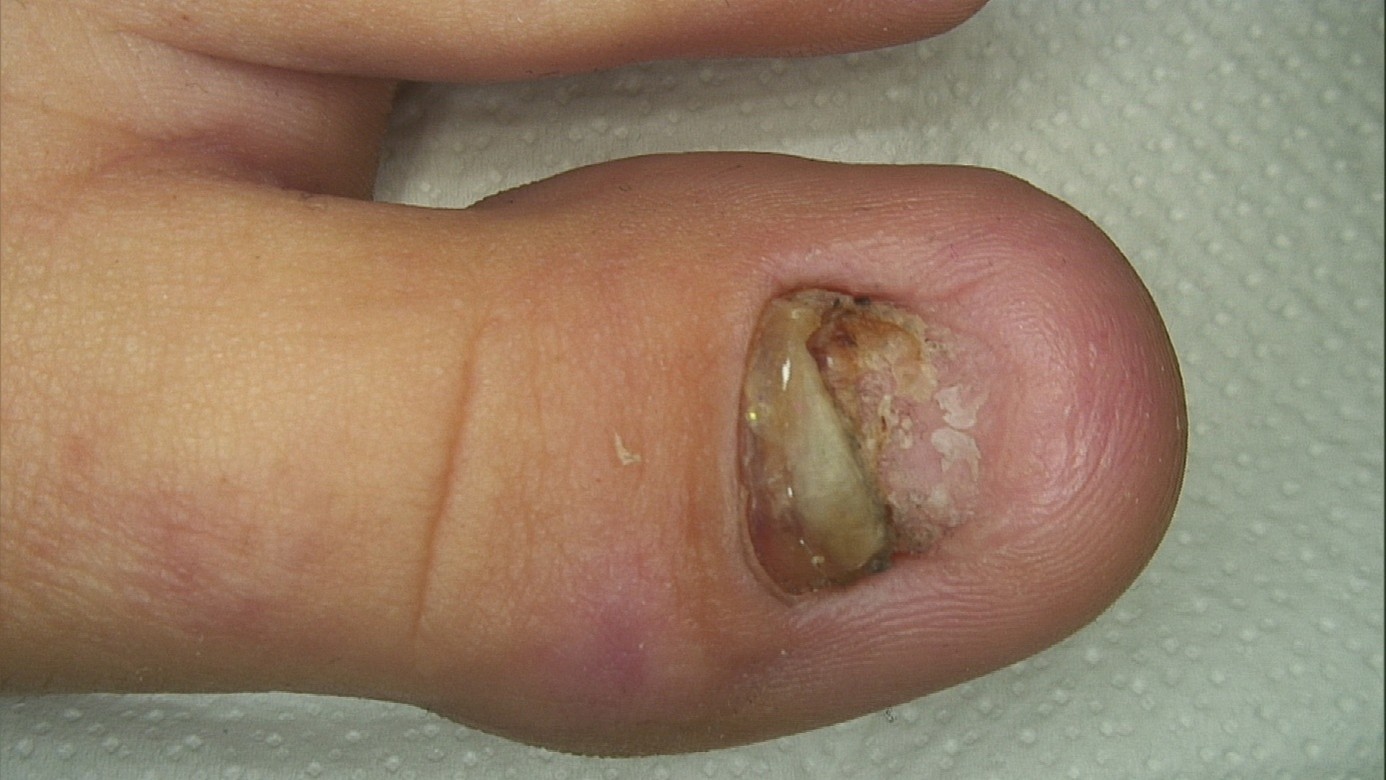

Pacijentica se javila zbog dugotrajnih promjena na noktima oba nožna palca koje su trajale gotovo devet godina. Promjene su nastale nakon traume nokta, a manifestirale su se žućkastom diskoloracijom, zadebljanjem nokatne ploče i djelomičnim odvajanjem nokta od podloge (oniholiza).

Unatoč prethodnoj terapiji antifungalnim preparatima nije došlo do poboljšanja. Dermatološkim pregledom postavljena je sumnja na retronychiju, poremećaj rasta nokta kod kojeg dolazi do nakupljanja nokatnih ploča i deformacije nokta.

U sklopu obrade učinjena je mikološka analiza nokta, koja je pokazala negativan nalaz na gljivičnu infekciju. Time je potvrđeno da promjene nisu uzrokovane onihomikozom, već poremećajem rasta nokta.